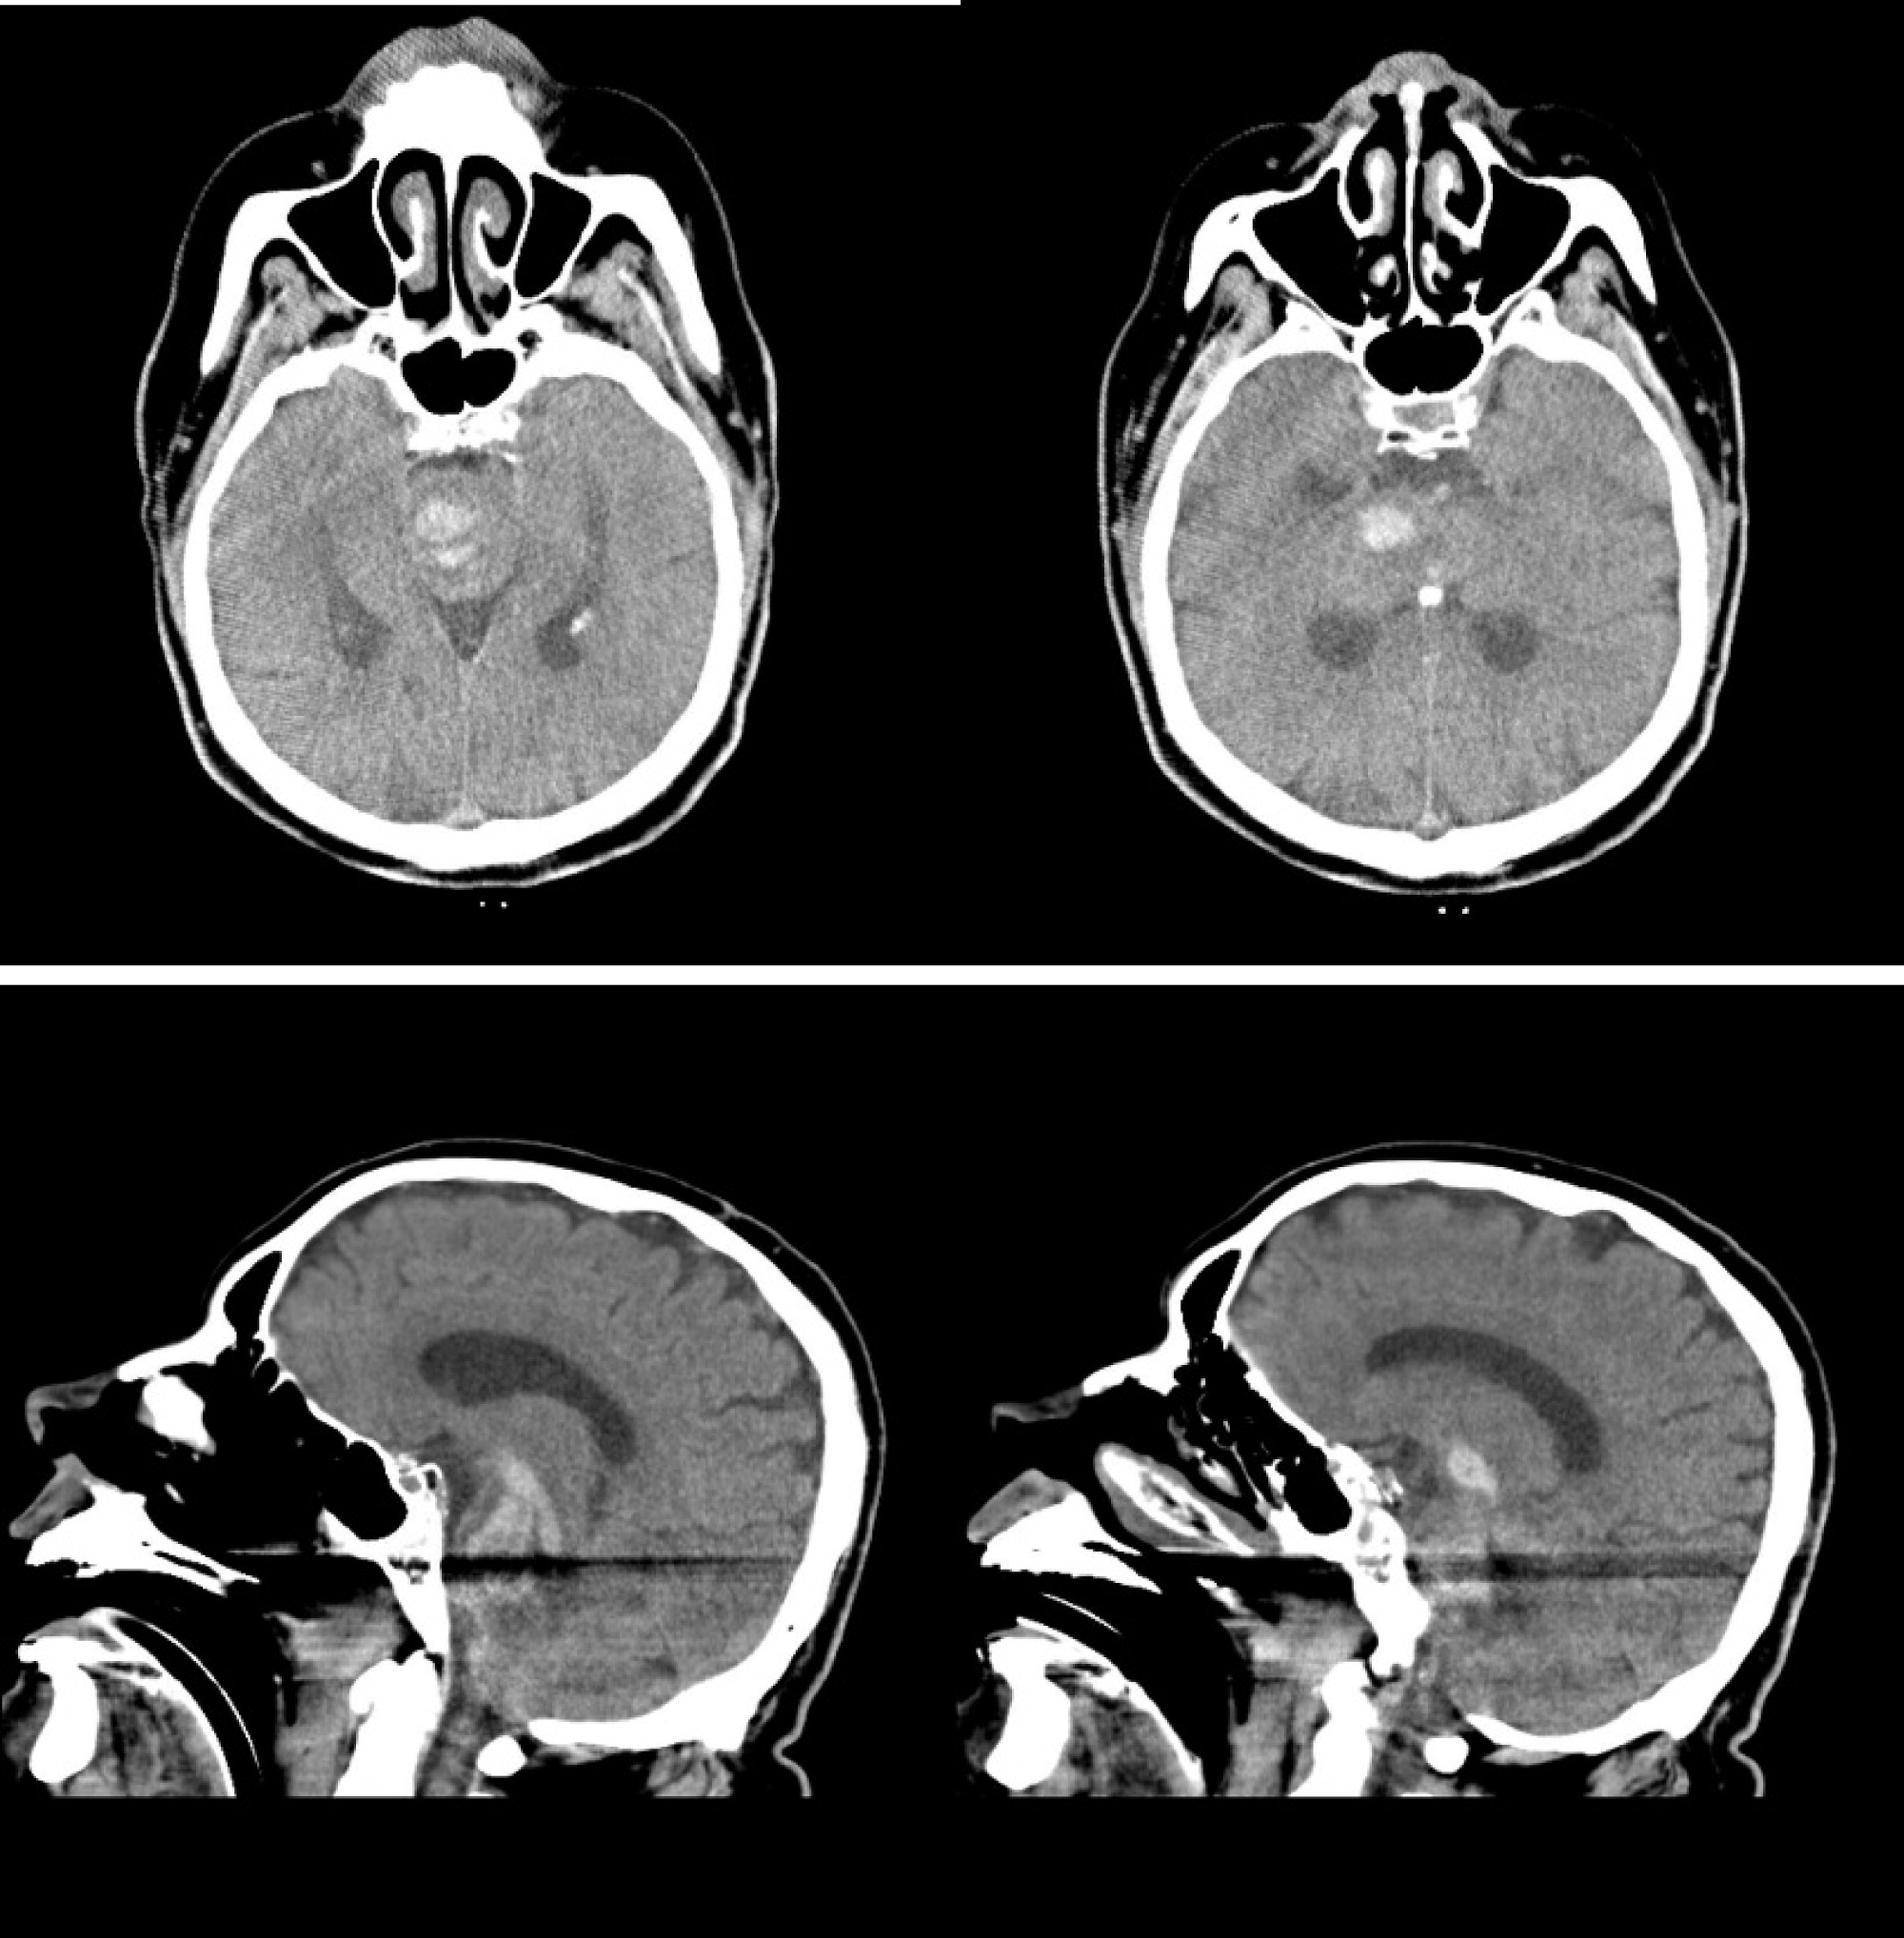

A 54-year-old male patient was admitted to the emergency department due to a loss of consciousness. According to the anamnesis taken from his wife, about 3-4 hours earlier, dizziness, nausea and vomiting started suddenly while chatting with her. Then the patient developed confusion and had difficulty understanding what others are saying. Finally, he was brought to the emergency department after the patient lost consciousness. According to information received from his wife, he received 2 sildenafil tablets (100 mg) 3 hours before the complaints started, to attempt sexual intercourse, but he could not. It was learned that there was no history of sildenafil use previously but he had an erection problem recently and It was prescribed by the urologist, to whom he applied on the recommendation of his wife. The patient had been normotensive and non-diabetic throughout his life. He had no hyperlipidemia. There was no drug use. He did not smoke, drink, or use illicit drugs. There was no drug addiction in the story taken from his family (cocaine etc.). His height was 1.77 meters and his weight was 81 kg. He had no family history of cerebral arteriovenous malformation, cerebral aneurysm or intracranial hemorrhage The neurological examination at presentation was as follows: Blood pressure was 130/85, heart rate was 104 and his fever was 37.1 The patient was confused, extension response to pain and making incomprehensible sounds. The Glasgow Coma Score was 6. Direct and indirect pupillary light reflexes were absent and he had small pupils, which are both ~1.5 mm bilaterally. There is no eye deviation. No asymmetry was observed in muscle strength and tonus examination. Reflexes are 2+ and symmetric at the biceps, triceps, knees, and ankles. There is no response to plantar reflex bilaterally. His breath sounds were bilaterally rough in auscultation. There was no significant feature in laboratory tests. Platelet count and coagulation factors were normal. Urine toxicological examination was not performed. Afterward, the patient developed respiratory distress in the emergency department and he was intubated. Then he was transferred to the neurology intensive care unit. ‎Cranial‎ computed‎ tomography ‎(CT)‎ scan ‎revealed a hyperdense hematoma area with vasogenic edema was detected. It was determined that the hematoma started from basal ganglia level and spread to mesencephalon and pons level inferior and to the 4th ventricle and pontocerebellar level in the posterior (Figure 1).

Figure 1: Computed‎ tomography ‎(CT)‎ scan and lateral section ‎of cranium for hyperdense hematoma area with vasogenic edema. View Figure 1

ICH secondary to sildenafil is a diagnosis of exclusion. The cranial CT angiography did not reveal any vascular anomalies or other reasons explaining the cause of ICH. In the medical history, we learned that the patient had no family history of cerebral arteriovenous malformation, cerebral aneurysm or intracranial hemorrhage.